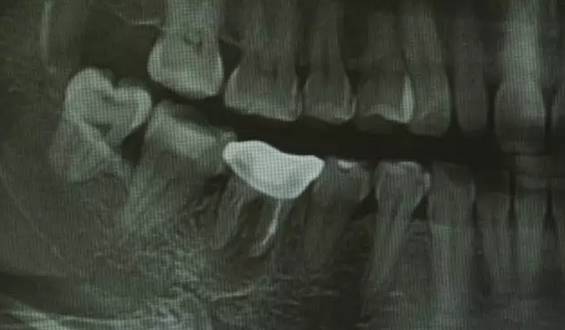

慢性根尖周肉芽肿慢性根尖周肉芽肿是根尖周组织受到轻微的感染刺激后产生的一团炎性肉芽组织。它是慢性根尖周炎的主要病变类型。一般无疼痛症状,有时有咀嚼乏力或不适。患牙多有深龋,牙髓多已坏死,牙齿变色,失去透明度,对冷、热诊及电诊均无反应,叩痛(—),但有时有异样感或叩痛,X线片示:有根尖周的骨质破坏区,即围绕根尖部的圆形或椭圆形边界清楚的透射区。

慢性根尖周脓肿慢性根尖周脓肿是慢性根尖周肉芽肿中央的细胞坏死、液化形成的脓肿;或急性根尖周脓肿处理不彻底,根尖部潴留的脓液被周围纤维结缔组织包绕而形成的。无窦型慢性根尖周脓肿症状与慢性根尖周肉芽肿大致相同,多无自觉症状。有窦型慢性根尖周脓肿患牙根尖部的颊、唇侧可见窦道口,窦道口也可能开口于远离患牙的位置,应仔细检查。X线片示:根尖部边界模糊的透射区,透射区周围骨质也较疏松。

慢性根尖周囊肿慢性根尖周囊肿是由慢性根尖周肉芽肿或慢性根尖周脓肿发展而来的。根尖囊肿生长缓慢,多无自觉症状。牙体可变黄色或深灰色,且无光泽,叩诊可有不适感,对冷、热诊及电诊均无反应;囊肿大小不等,发展较大时,可见根尖部相应软组织膨隆,表面不红,扪压富于弹性,有乒乓球感;囊肿过于肥大时,周围骨质被压迫吸收,可引起牙齿松动,或压迫邻牙使牙根吸收或邻牙移位。X线片示患牙根尖有圆形透射区,边界清楚,周围有白线围绕,此为诊断的重要依据。较小的根尖周囊肿与根尖周肉芽肿不好区分,大的根尖周囊肿应与颌骨囊肿及造釉细胞瘤相鉴别。